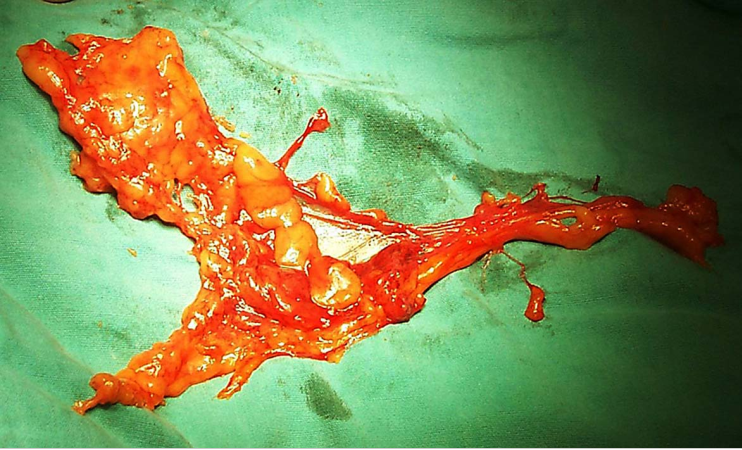

1.手术治疗 手术的优点是年轻患者可保留卵巢及阴道功能。主要用于早期子宫颈癌(ⅠA~ⅡA期)患者。①ⅠA1期:无淋巴脉管间隙浸润者行筋膜外全子宫切除术,有淋巴脉管间隙浸润者按ⅠA2期处理。②ⅠA2期:行改良广泛性子切除术及盆腔淋巴结切除术或考虑前哨淋巴结绘图活检(sentinel lymphnode mapping)。③ⅠB1期、和ⅠB2期ⅡA1期:行广泛性子宫切除术及盆腔淋巴结切除术或考虑前哨淋巴结绘图活检,必要时行腹主动脉旁淋巴取样。④部分ⅠB2期和ⅡA2期:行广泛性子宫切除术及盆腔淋巴结切除术和选择性腹主动脉旁淋巴结取样;或同期放、化疗后行全子宫切除术;也有采用新辅助化疗后行广泛性子宫切除术及盆腔淋巴结切除术和选择性腹主动脉旁淋巴结取样。未绝经、<45岁的鳞癌患者可保留卵巢。要求保留生育功能的年轻患者,ⅠA1期无淋巴脉管间隙浸润者可行子宫颈锥形切除术(至少3cm阴性切缘);ⅠA1期有淋巴脉管间隙浸润和ⅠA2期可行子宫颈锥形切除术加盆腔淋巴结切除术或考虑前哨淋巴结绘图活检,或和ⅠB1期处理相同;一般推荐ⅠB1期行广泛性子宫颈切除术及盆腔淋巴结切除术或考虑前哨淋巴结绘图活检,但若经腹或腹腔镜途径手术,手术指征也可扩展至ⅠB2期。

Ⅲ型即广泛子宫切除术标本 盆腔淋巴结切除术标本

广泛子宫颈切除术切除的子宫颈及宫旁组织 广泛子宫颈切除术后功能重建的子宫及双附件